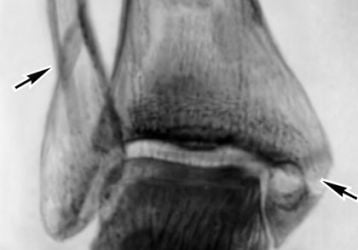

Посттравматический артроз голеностопного сустава: симптомы и лечение

Посттравматический артроз голеностопного сустава. Причины заболевания, симптомы проявления. Способы лечения, список препаратов.